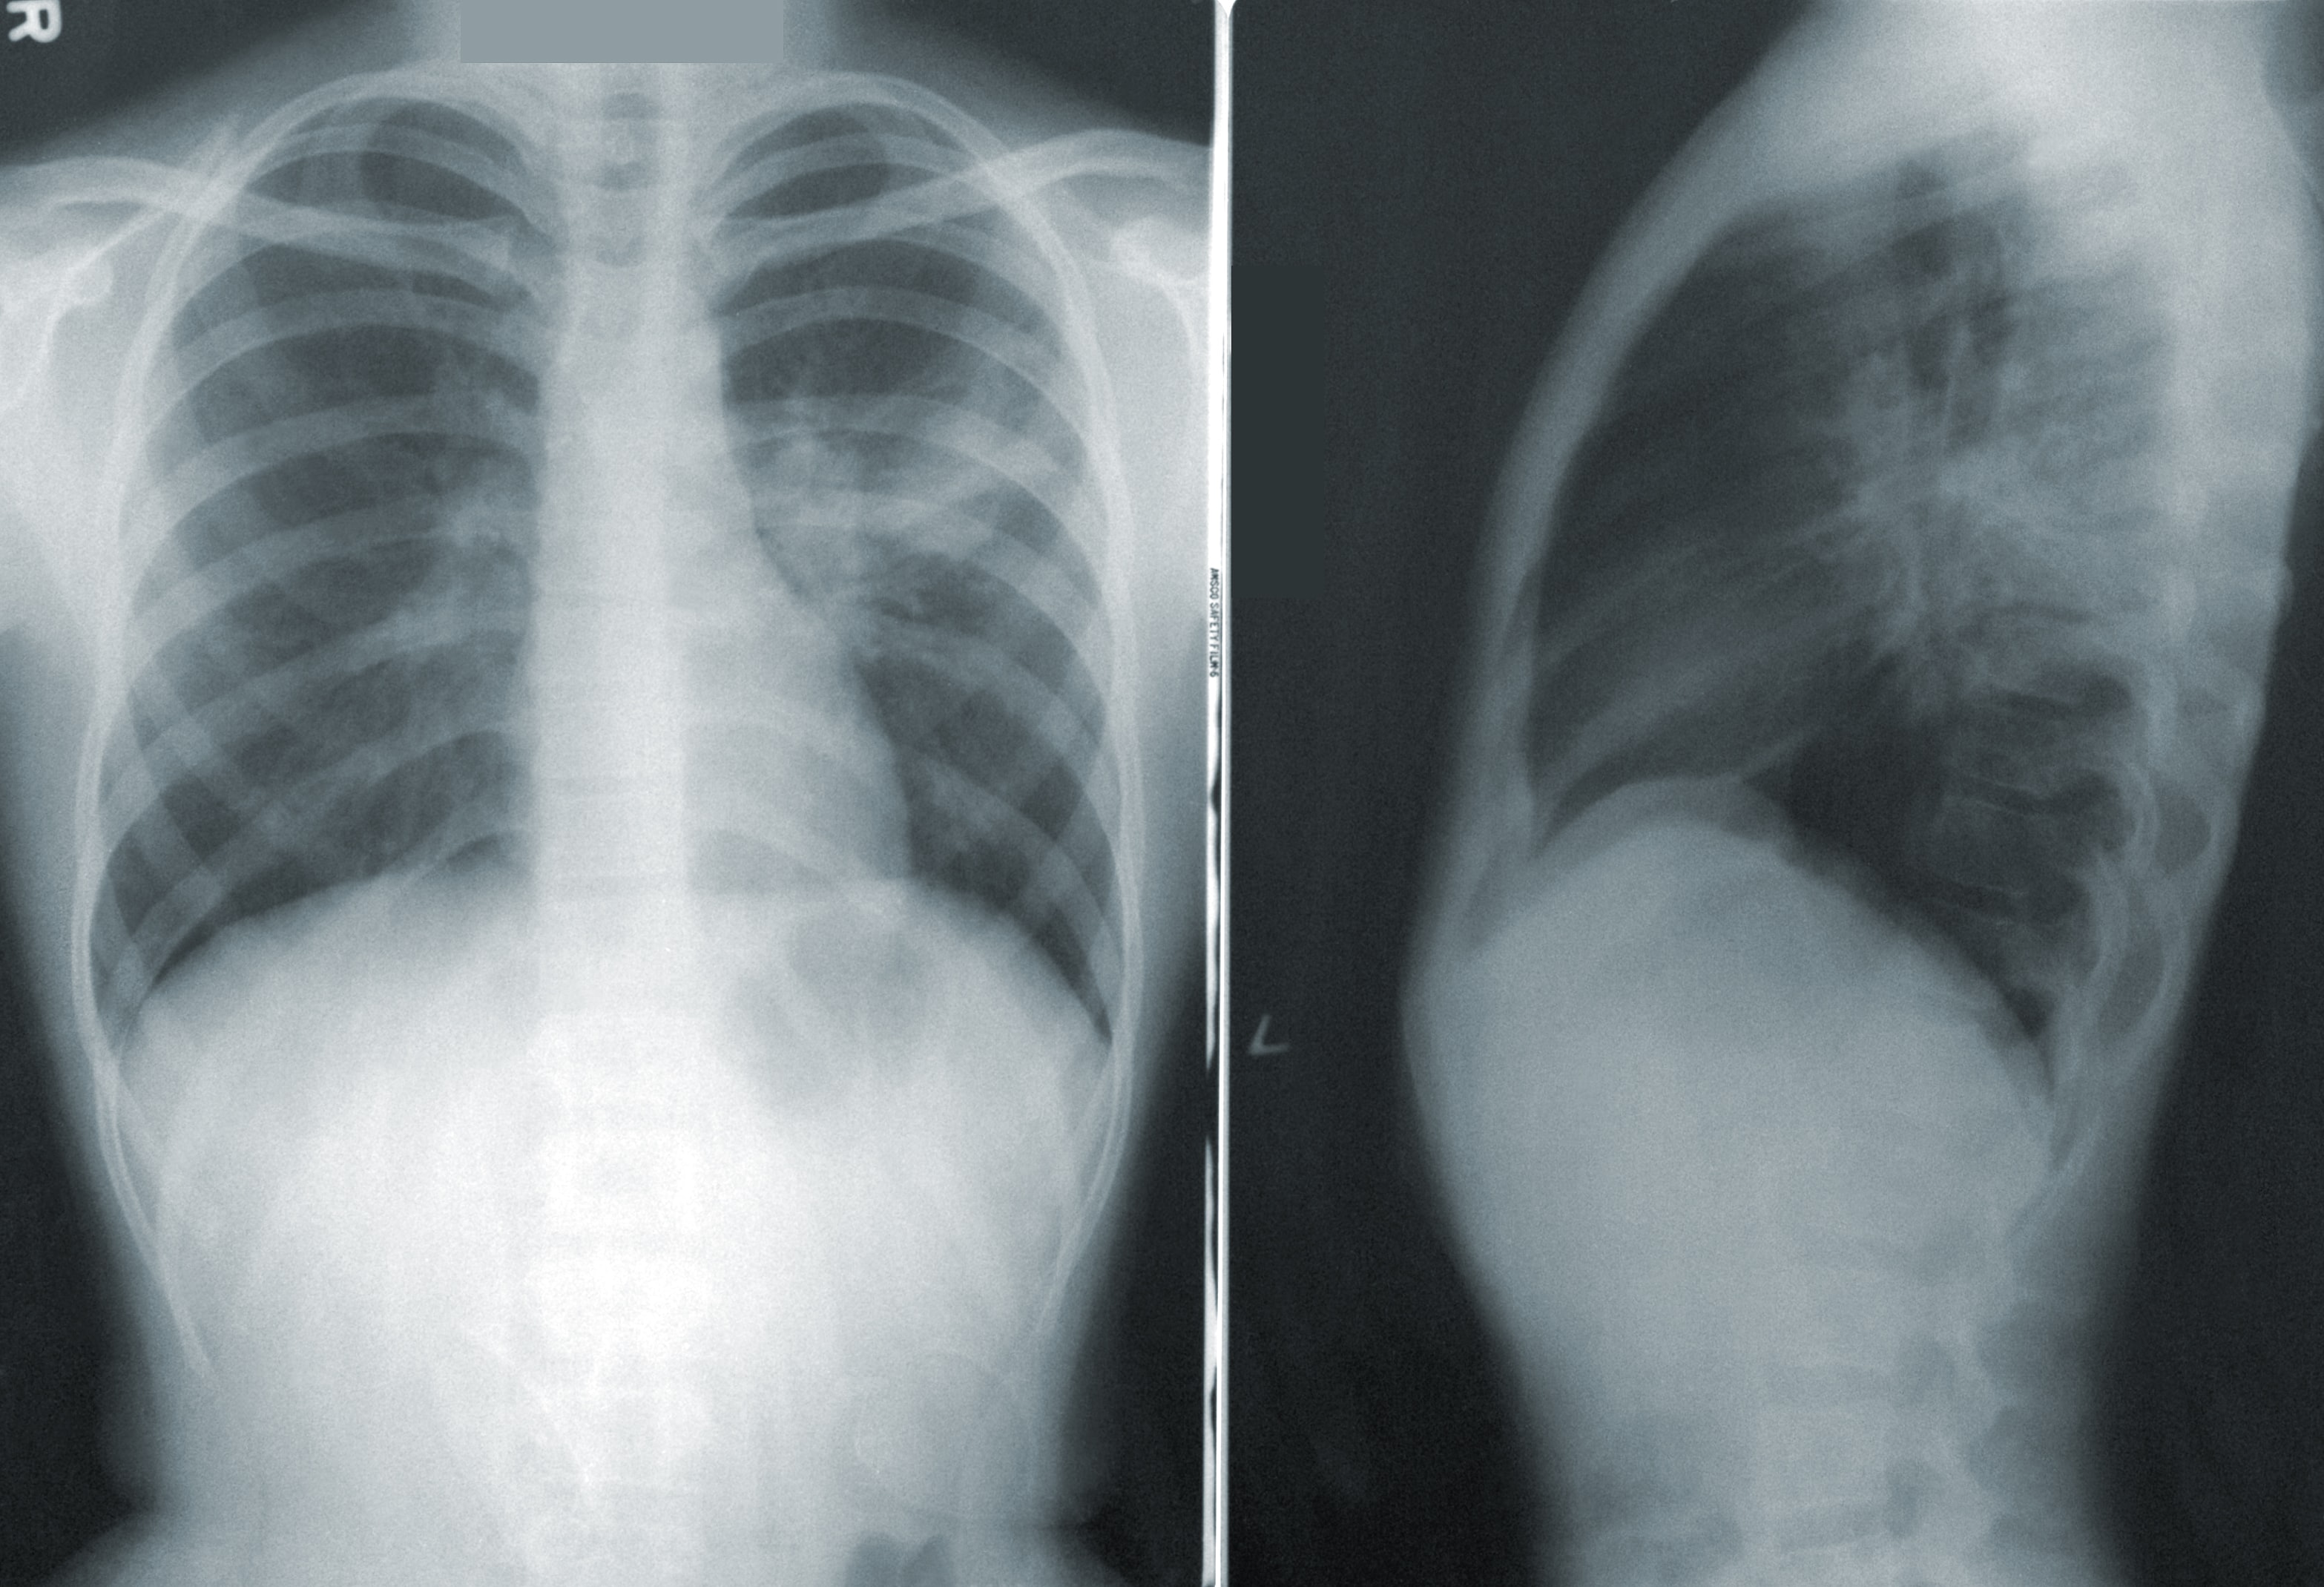

The most frequent cause of COPD risk is cigarette smoking. Smoking causes COPD in 80% of cases, and 20% of smokers will likely develop the disease. Information on smoking, including frequency, intensity, and the number of years since quitting for former smokers, may be crucial in evaluating the risk of COPD.

Smoking harms your lungs\' air sacs, airways, and lining. It is challenging to breathe when the lungs are injured because not enough air can enter or exit. Additionally, smoking might cause flare-ups of COPD.